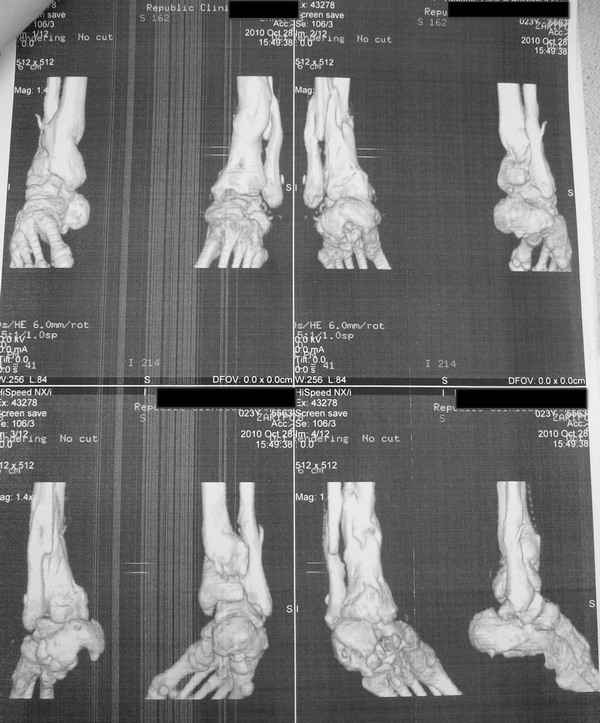

Молодая девушка со сросшимися многооскольчатыми переломами пяток и голеней.

Young girl with fractures of the calcaneus

Больная Н., 25 лет, падение с высоты (2008 г.). Жалобы на боли в области голеностопных суставах, в области пяток при ходьбе. Лечилась в аппаратах внешней фиксации по поводу открытых оскольчатых переломов обеих голеней, переломов пяток. Далее по поводу несросшихся переломов голеней –ЧКОС аппаратами внешней фиксации. Переломы срослись, аппараты демонтированы весной 2010г. В левой пяточной области в месте проведения спицы имеется сукровичное отделяемое. При ревизии гноя нет. Чем помочь девушке?

Patient N., age 25, falls from heights (2008). Complaints of pain in the ankles, in the heel when walking. She was treated by external fixation on open comminuted fractures of both legs, fractures of the calcaneus. Then she was treated by external fixation from nonunion of both legs. Now fractures are fused, apparatuses removed in the spring of 2010. How to help a girl?